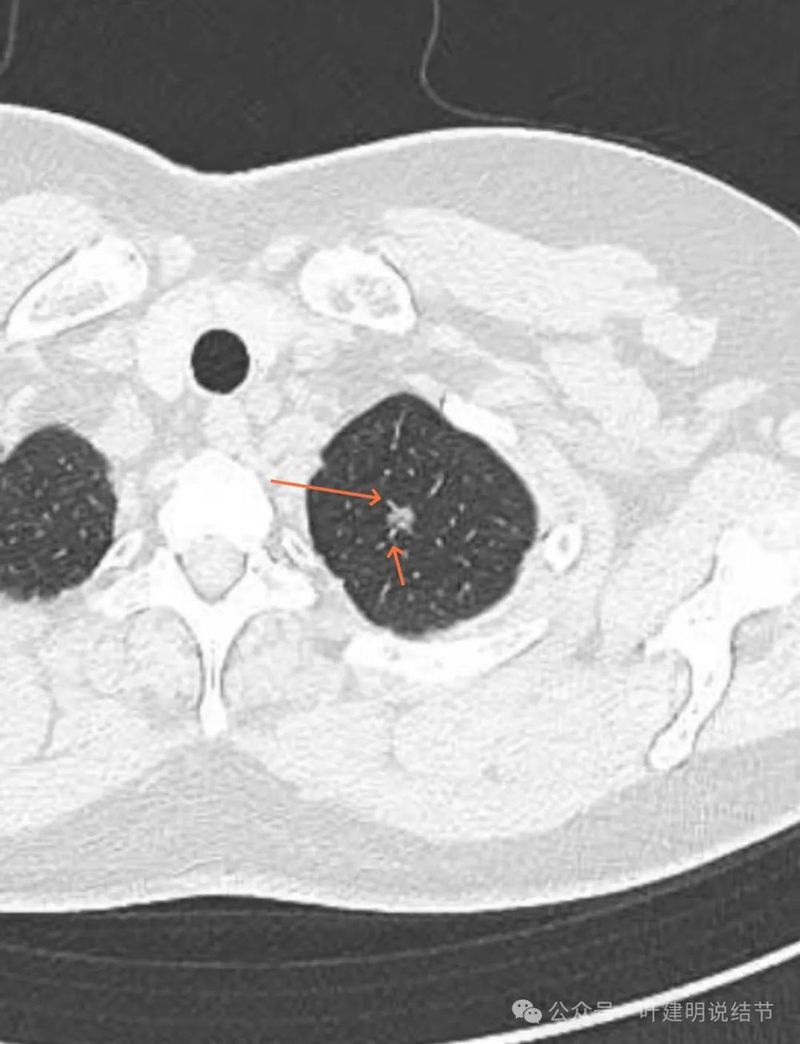

血管进入,小棘突征,密度不均,轮廓与边界清。

血管进入明显,此层密度不太致密,更偏高磨玻璃点。

磨玻璃密度,边缘毛刺、血管贴边与穿行,小血管进入、病灶边缘有细支气管扩张。